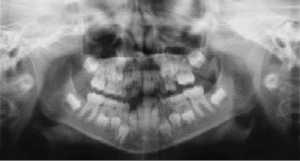

Radiographs (X-Rays) are a vital and necessary part of your child’s dental diagnostic process. Without them, certain dental conditions can and will be missed.

Radiographs detect much more than cavities. For example, radiographs may be needed to survey erupting teeth, diagnose bone diseases, evaluate the results of an injury, or plan orthodontic treatment. Radiographs allow dentists to diagnose and treat health conditions that cannot be detected during a clinical examination. If dental problems are found and treated early, dental care is more comfortable for your child and more affordable for you.

The American Academy of Pediatric Dentistry recommends radiographs and examinations every six months for children with a high risk of tooth decay. On average, most pediatric dentists request radiographs approximately once a year. Approximately every 3 years, it is a good idea to obtain a complete set of radiographs, either a panoramic and bitewings or periapicals and bitewings.

Pediatric dentists are particularly careful to minimize the exposure of their patients to radiation. With contemporary safeguards, the amount of radiation received in a dental X-ray examination is extremely small. The risk is negligible. In fact, the dental radiographs represent a far smaller risk than an undetected and untreated dental problem. Lead body aprons and shields will protect your child. Today’s equipment filters out unnecessary x-rays and restricts the x-ray beam to the area of interest. High-speed film and proper shielding assure that your child receives a minimal amount of radiation exposure.